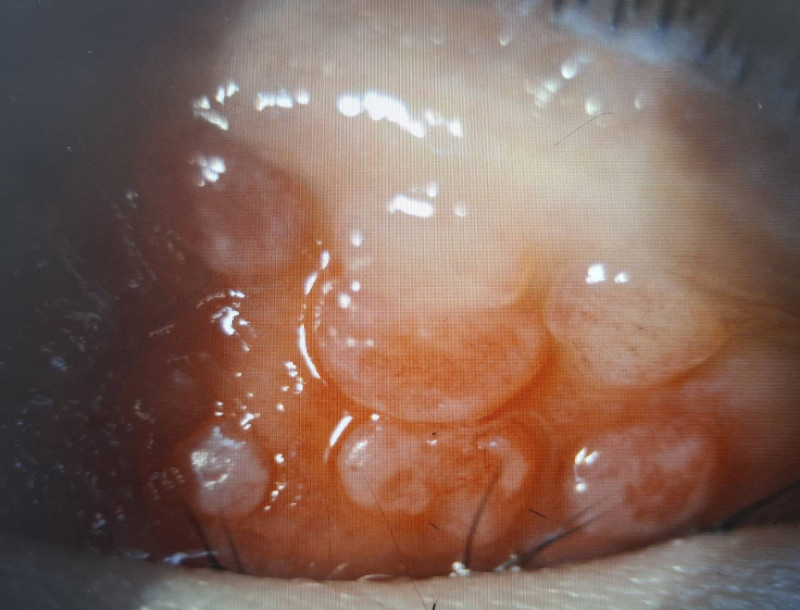

男童因結膜慢性發炎,使結膜上皮細胞的過度增生,長成大於0.1公分的乳突。(洪啟庭提供)

巨大乳突壓迫不僅造成角膜潰瘍,還出現高度散光而視力模。(洪啟庭提供)

達特楊眼科聯盟執行長洪啟庭指出,小二男童就醫時不僅左眼眼瞼嚴重腫脹,最佳視力僅0.5並有300度散光,應是過敏性結膜炎合併過敏性鼻炎、濕疹、異位性皮膚炎或氣喘等,因為長期揉眼導致眼皮長滿巨大乳突,因長時間壓迫造成上半部角膜有淺層潰瘍,故造成300度的高度散光和視力模糊,經強效抗生素與適當類固醇藥水治療,2星期後角膜潰瘍痊癒,乳突的也變小,學童眨眼睛的現象也明顯改善,但乳突完全消失恐要半年以上。

洪啟庭表示,台灣地區每3個學童就有1位罹患短期或長期性過敏性結膜炎,短期多是季節性過敏,長期性因慢性發炎,使結膜上皮細胞的過度增生,如本案男童長成大於0.1公分的乳突,病人會有明顯的異物感、激癢、黏液分泌物變厚、視力模糊,嚴重時還會出現角膜潰瘍。成人大多是和隱形眼鏡配戴習慣不良有密切關係,學童多為過敏反應。